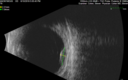

88 year old female with melanosis oculi and 2.5 mm elevated choroidal melanoma. She also has AMD with geographic atrophy. The right eye is the better eye. The left eye had a macular hemorrhage from wet AMD and breakthrough vitreous hemorrhage.